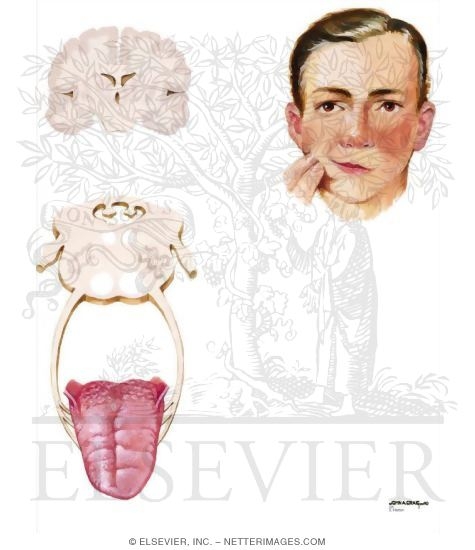

Hypoglossal Nerve (CN-XII)

Hypoglossal Nerve (CN-XII)

Hypoglossal Nerve (CN-XII)

Hypoglossal Nerve (CN-XII)